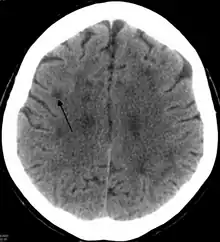

Scanner montrant une leucoencéphalopathie probablement due à une ischémie des petits vaisseaux. La flèche n'indique qu'une zone parmi d'autres.